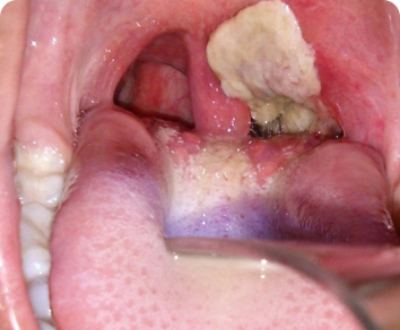

Bạch hầu là bệnh gì? Bạch hầu là bệnh nhiễm độc cấp tính gây ra do vi khuẩn Corynebacterium diphtheriae, có triệu chứng đặc trưng là xuất hiện giả mạc ở tuyến hạnh nhân, hầu họng, thanh quản, mũi, trên da và các màng niêm mạc khác như kết mạc mắt, bộ phận sinh dục…